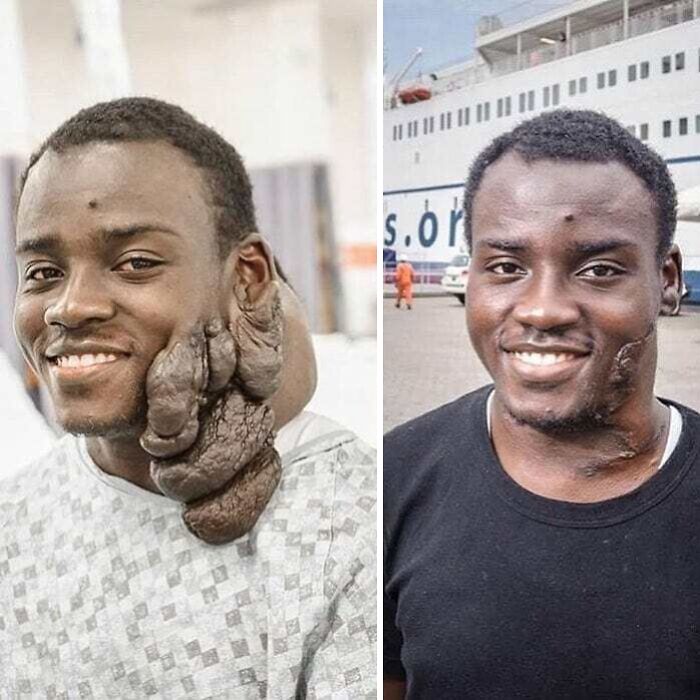

#7 Devätnásťročný Bernard podstúpil operáciu, na ktorej mu odstránili výrastok na tvári, ktorý tam mal viac ako desať rokov